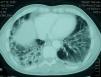

La tomografia axial computarizada de alta resolución fue informada como enfermedad intersticial difusa de predominio periférico en relación con probable neumonía organizada criptogenética (NOC) (fig. 3). Se recibieron los autoanticuerpos, que aclararon el diagnóstico: anticuerpos anti-Jo1 de 376U/ml [N: 0–80], antinucleares 1/320, factor reumatoide 41,8U/ml. Iniciamos tratamiento con metilprednisolona (1mg/kg/día). El estudio electromiográfico fue normal y la espirometría manifestó un patrón restrictivo moderado con la capacidad de difusión del monóxido de carbono disminuida.